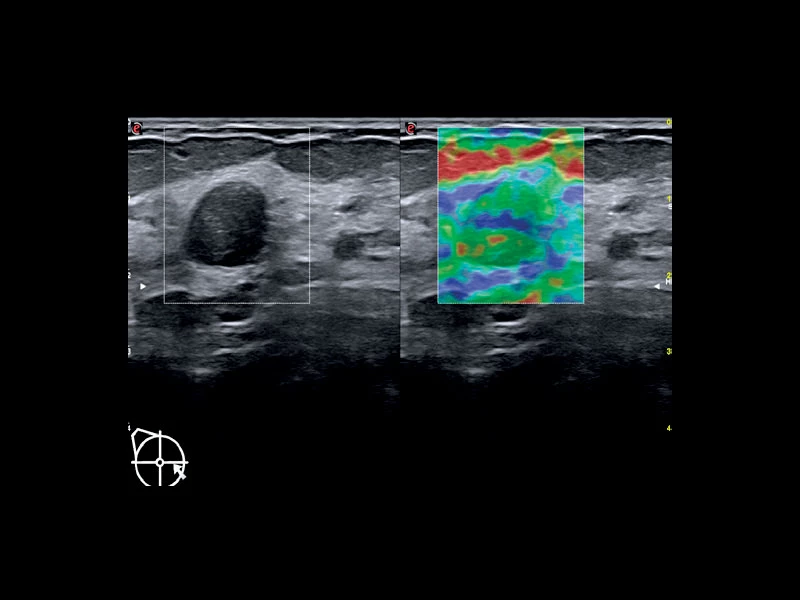

MyLab™9 Platform - Dual ElaXto characterization on breast lesion

MyLab™9 Platform - Dual ElaXto characterization on breast lesion